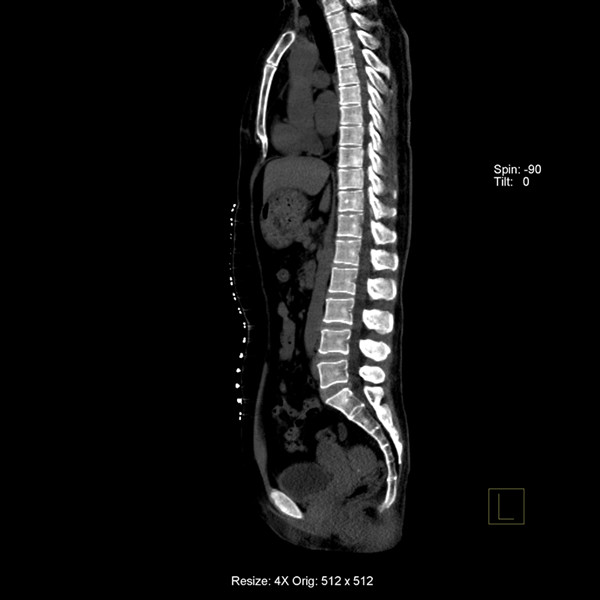

炫速雙源CT是目前世界上最先進的CT設(shè)備之一。它采用兩套64排圖像采集系統(tǒng),結(jié)合“飛焦點”技術(shù),并且有超高的旋轉(zhuǎn)速度,能夠在極短的時間內(nèi)完成掃描,為病人提供“綠色” CT 檢查。它的特點是炫速掃描技術(shù) (Flash Spiral),即大螺距的螺旋掃描,可以在一秒鐘之內(nèi)完成掃描,同時輻射劑量極低。 它的主要特色掃描技術(shù)如下:

7、病人因胸痛急診時,快速獲得準(zhǔn)確的診斷是關(guān)鍵。對于具有極高時間分辨率的炫速雙源CT來說,不但可以輕松完成常規(guī)檢查,而且可以對特別嚴(yán)重的急診患者完成“一站式”診斷,對急性胸痛患者通過一次注射對比劑同時獲得冠脈CTA、肺動脈CTA及主動脈CTA,可明確胸痛病因是心臟冠脈疾病、肺動脈栓塞還是主動脈夾層,具有非常實用的臨床價值。